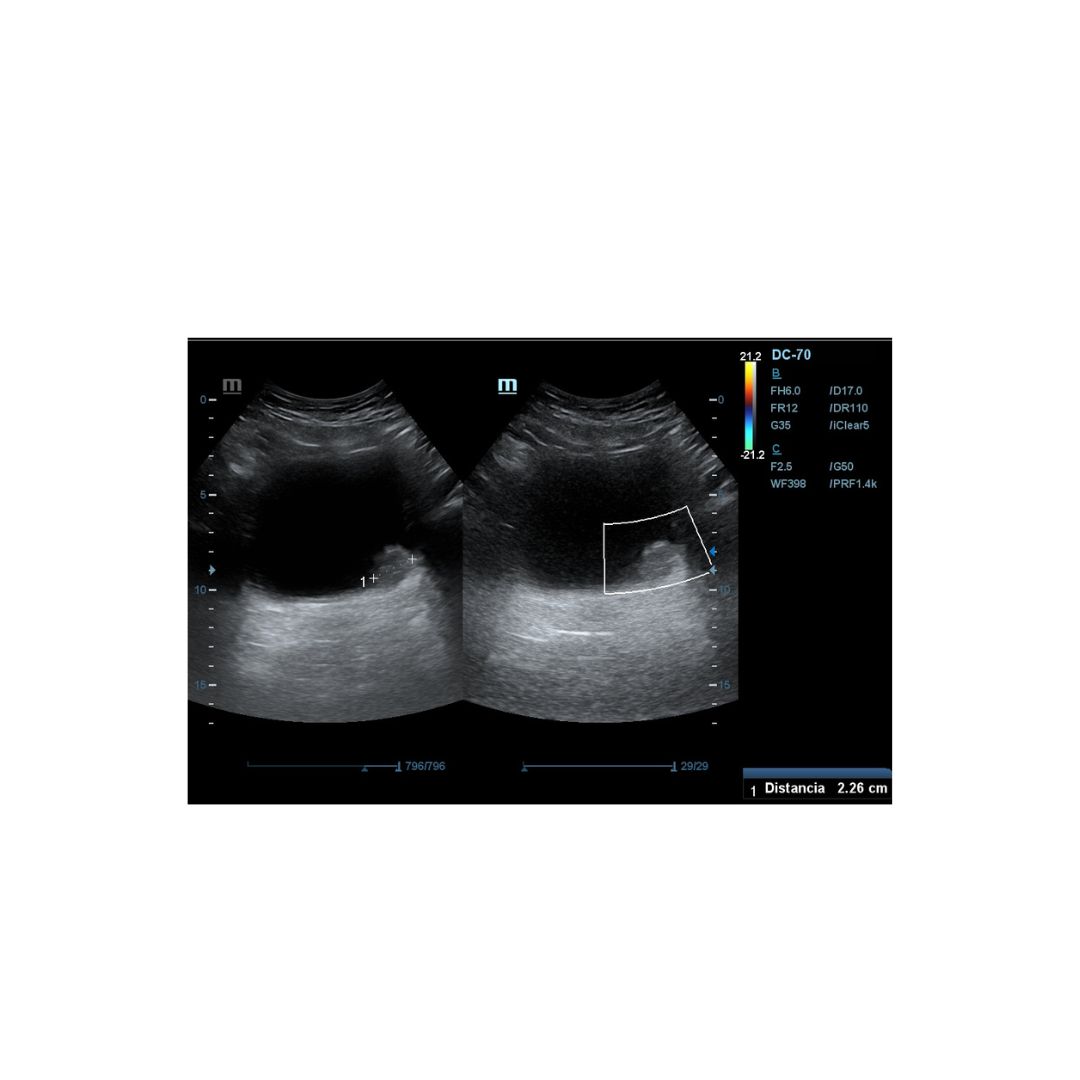

Es derivado a consulta de ecografía de nuestro centro de salud, donde realizamos Ecografía clinica abdominal, apreciándose imagen hiperecogénica pediculada en pared posterior izquierda de la vejiga vejiga, fija, que mide 2,26 mm aproximadamente en su eje mayor, sin captación Doppler.